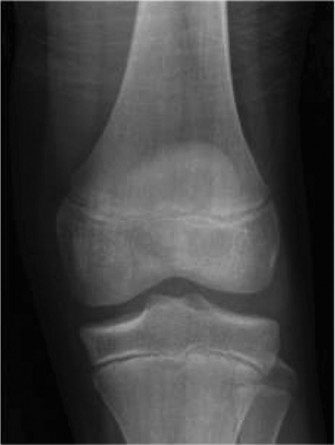

CASE 9 A 14-year-old boy is brought to the ER with complaints of right knee pa…